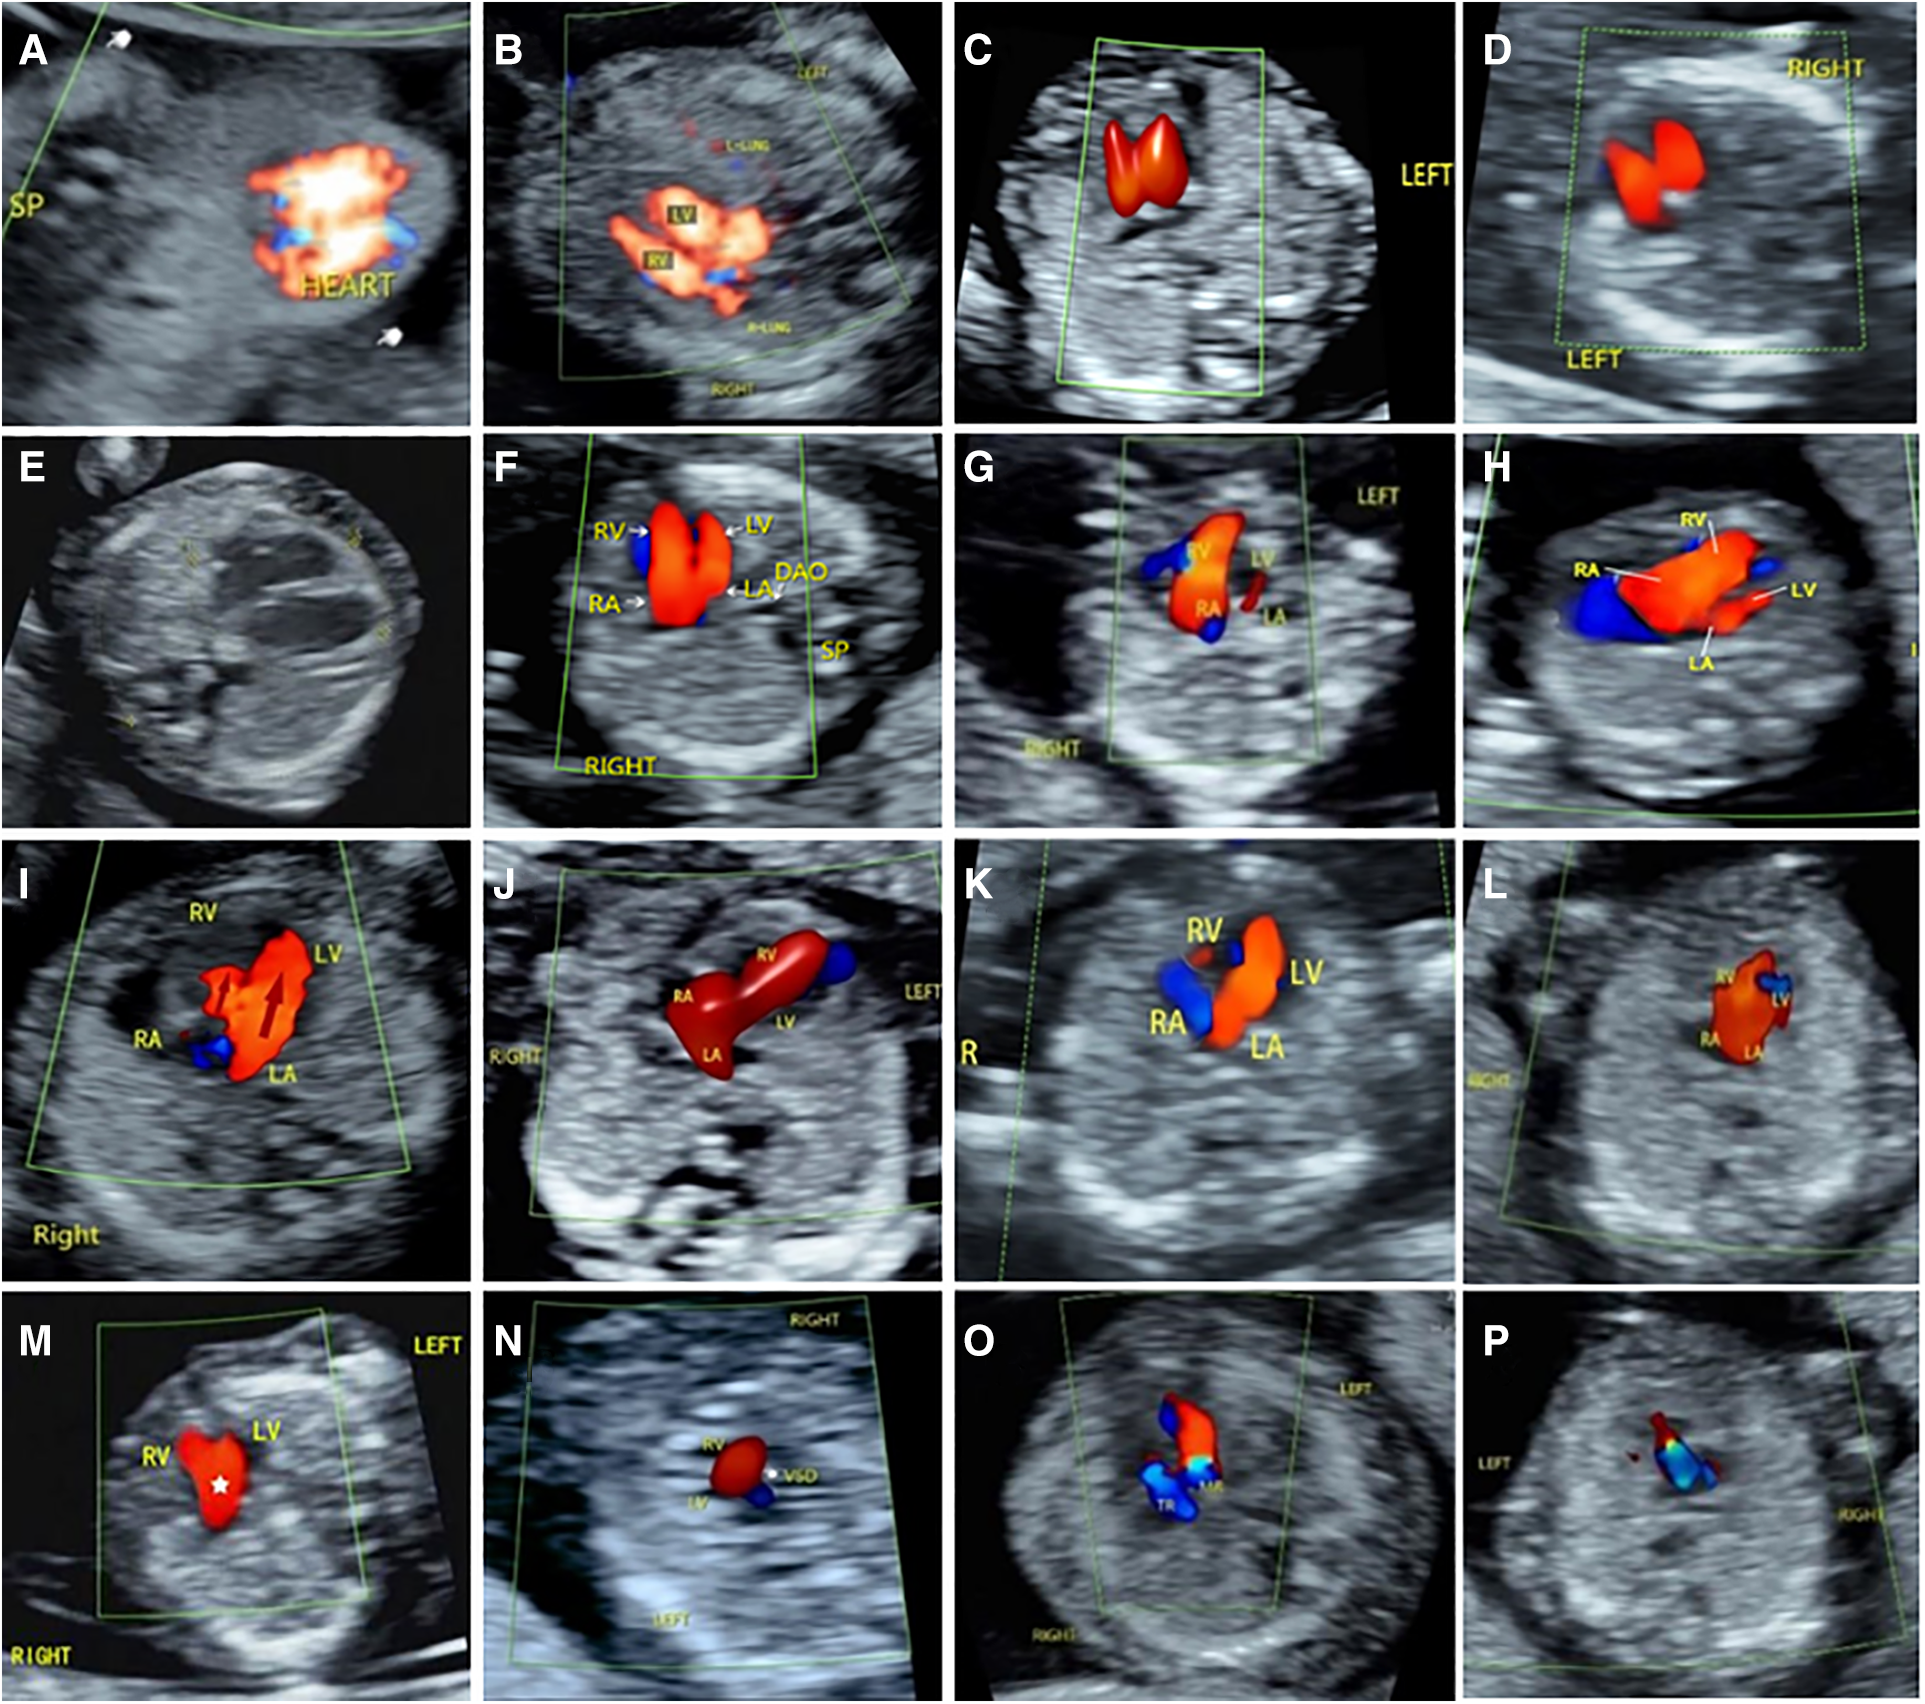

Among the 176 fetuses with CHD, 10 fetuses had an abnormal upper abdominal transverse section. According to the integrity of the fetal abdominal wall and the spatial position of four U-shaped structures (gastric bleb, inferior vena cava, aorta, and spine), four abnormal image patterns of UAb transverse section were found, which could be seen in normal cases, situs inversus, left isomerism syndrome, and right isomerism syndrome (Figure 4). According to the location, size, cardiac axis, the central crisscross structure of the heart and the size and direction of blood flow bundles, 16 kinds of 4CV section abnormal patterns were found (Figure 5). According to the number of large arteries, the relationship between the pulmonary artery and the aorta, the diameter of the pulmonary artery and the aorta, and the direction of blood flow between the ductus arteriosus and the aortic arch, eight abnormal patterns of 3VT section were found (Figure 6). According to the course of bilateral subclavian arteries, two abnormal patterns of BSa sections were found (Figure 7).

Figure 5

Abnormal ultrasound image pattern of 4CV section. (A) Patterns of 4CV-1 showed that the heart is partially or completely located outside the chest cavity. (B) Patterns of 4CV-2 showed displacement of heart. (C) Patterns of 4CV-3: the cardiac axis is abnormally shifted to the forward. (D) Patterns of 4CV-4: The cardiac axis is abnormally shifted to the right. (E) Patterns of 4CV-5 indicate an increase in cardiothoracic ratio. (F) Patterns of 4CV-6, filling of both ventricles, but the left ventricle appears smaller. (G) Patterns of 4CV-7: The left heart is spherically enlarged, and the filling of left ventricle appears smaller. (H) Patterns of 4CV-8: The filling of the right heart increased obviously. (I) Patterns of 4CV-9, filling of both ventricles, but the right ventricle appears very smaller. (J) Patterns of 4CV-10, filling of only the right ventricle. (K) Patterns of 4CV-11, filling of only the left ventricle. (L) Patterns of 4CV-12 showed a central singular inflow. (M) Patterns of 4CV-13 indicate “Y”-shaped filling of the ventricular inflow tract during diastole. (N) Patterns of 4CV-14 indicate a ventricular septal defect. (O) Patterns of 4CV-15, mitral or tricuspid regurgitation. (P) Patterns of 4CV-16, common valve regurgitation in atrioventricular septal defect.

With the improvement of ultrasonic instrument resolution and blood flow imaging mode, the imaging ability of cardiac structure in early pregnancy has been significantly optimized. Previous studies have described the most common abnormal blood flow patterns of the 4CV section and 3VT section in fetuses of 11–13+6 weeks by two-section method (14), which will significantly promote the development of cardiac screening in early pregnancy. This study analyzed CHD’s ultrasonic characterizations based on the four-section approach at 11–13+6 weeks and further complemented the pattern of abnormal images. We summarized the four abnormal image patterns in the upper abdominal transverse section, representing the four types of abnormalities. The observation of the size and location of the gastric vesicle in the transverse section of the upper abdomen and the location of the inferior vena cava and abdominal aorta plays an important role in determining the position of the viscera, which can assist in the diagnosis of the isomeric syndrome (20, 21). 4CV section abnormalities were most common in the inflow tract of the heart. The abnormal image patterns of 4CV section can be divided into eight categories. Irregular heart size is mainly manifested as the increased cardiothoracic ratio, and heart failure caused by severe valvular regurgitation is expected in early pregnancy. The abnormal balance of left and right ventricular blood flow bundles can be divided into right heart dominant and left heart dominant. Right heart dominance is mostly caused by coarctation of the aortic arch, hypoplastic aortic arch, or interrupted aortic arch. In addition, tricuspid valve developmental abnormalities such as Ebstein’s anomaly may contribute to the right heart-dominant flow pattern in early pregnancy. Some studies have shown that right heart dominance is also seen in atrioventricular junction inconsistencies or related to partial proper ventricular double outlet (22). Left heart dominance is common in right ventricular dysplasia, but it is also a sign of severe aortic stenosis (23). Since some valvular pathologies are progressive, it is essential to regularly review and monitor the asymmetry of the left and right ventricular flow bundle widths. A single blood flow bundle in the heart is a manifestation of severe CHD (14). The single arterial blood flow bundle is vertically oriented, suggesting a pulmonary bundle, which is common in HLHS; if the single arterial blood flow bundle is curved to the side, it suggests an aortic arch blood flow bundle, which is common in conotruncal defects. Due to the aliasing of left and right ventricular blood flow bundles, it is difficult to show the transseptal blood flow bundles of the ventricular septal defect in early pregnancy. If suspicious cases are found based on grayscale ultrasound, multi-section scanning and follow-up are needed. Mitral and/or tricuspid valve regurgitation are often transient, and mild atrioventricular valve regurgitation can be easily missed by color Doppler observation alone. Therefore, it is important to routinely use pulsed Doppler for standard sampling. When 4CV section abnormalities are found, further careful evaluation of 3VT section should be performed.